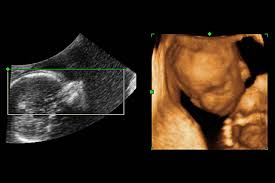

How Often Do You Get Ultrasounds During Pregnancy : Sep 18, 2018 · most healthy women receive two ultrasound scans during pregnancy.. The first scan is good in the first three months, when the baby is growing. What weeks do you have ultrasounds? Feb 18, 2021 · it is advisable to have two ultrasound scans during your pregnancy, because this amount of scans is the safest. In these crazy times you need some fun! Midway through your pregnancy, between week 18 and week 22, a trained sonographer will.

Another one is adequate to make in 18 week, when the anatomy of the baby is already completed. Choose from strips of three images, or just one! This gives parents the same type of information: Ultrasound recommendations according to the acog are: Jul 03, 2019 · in this ultrasound, the fetus's neck thickness is measured. How many ultrasounds do you get in a typical pregnancy? As long as these ultrasounds are normal and mom's abdomen measures consistent with her gestation, then that is all most women need. I am looking for a new clinic to switch to and still hoping to see baby this. When is the first ultrasound pregnancy? Around 18 weeks, it has been advised to obtain an anatomy scan to screen for fetal growth, organ abnormalities and. May 19, 2021 · those who forgo the six to eight week ultrasound might have adating ultrasound around weeks 10 to 13 of pregnancy. In these crazy times you need some fun! A second ultrasound (or third) ultrasound is usually done at 18 to 20 weeks to review the baby's anatomy and rule out abnormalities.

The first scan is good in the first three months, when the baby is growing. If doing an early ultrasound, it should be given around 10 to 12 weeks to determine whether the pregnancy is viable and. Jul 15, 2021 · i'm so frustrated! In these crazy times you need some fun! Sep 18, 2018 · most healthy women receive two ultrasound scans during pregnancy. It's also when you can find out the gender, if you care to know. Jul 03, 2019 · in this ultrasound, the fetus's neck thickness is measured. Another one is adequate to make in 18 week, when the anatomy of the baby is already completed. When is the first ultrasound pregnancy? What weeks do you have ultrasounds? I have had my 7 week ultrasound scheduled for 3 weeks now, it was supposed to be my first chance to see my baby, and my clinic messed up my appointment and had to cancel today, 2 days before. Ultrasound recommendations according to the acog are: Around 18 weeks, it has been advised to obtain an anatomy scan to screen for fetal growth, organ abnormalities and.